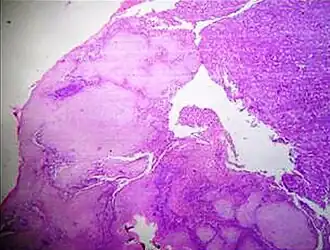

A crush artifact is an artificial elongation and distortion seen in histopathology and cytopathology studies, presumably because of iatrogenic compression of tissues. Distortion can be caused by the slightest compression of tissue and can provide difficulties in diagnosis.[2][3] It may cause chromatin to be squeezed out of nuclei.[4] Inflammatory and tumor cells are most susceptible to crush artifacts.[4]

Crush artifact from compression by forceps on the tissue sample -

Folding artifacts (white arrows) and a crush artifact (black arrow, with cytoplasmic hypereosinophilia and nuclear pleomorphism) from a needle -